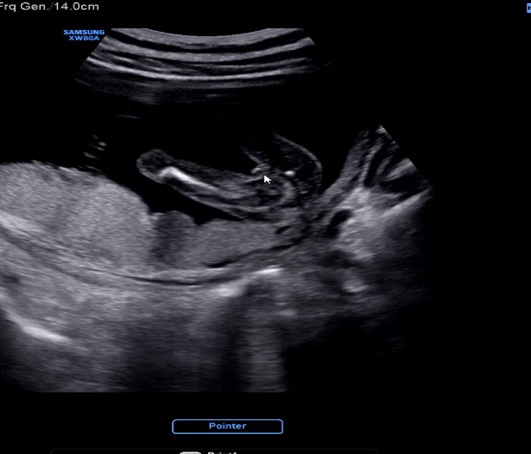

W20 임산부 일상 (임신 20주 정밀초음파)

12.9(금) 20주 6일 정기진료날 휴가를 내고 남편이랑 부랴부랴 병원으로 출발했다 병원에 가면 늘 하는 루...